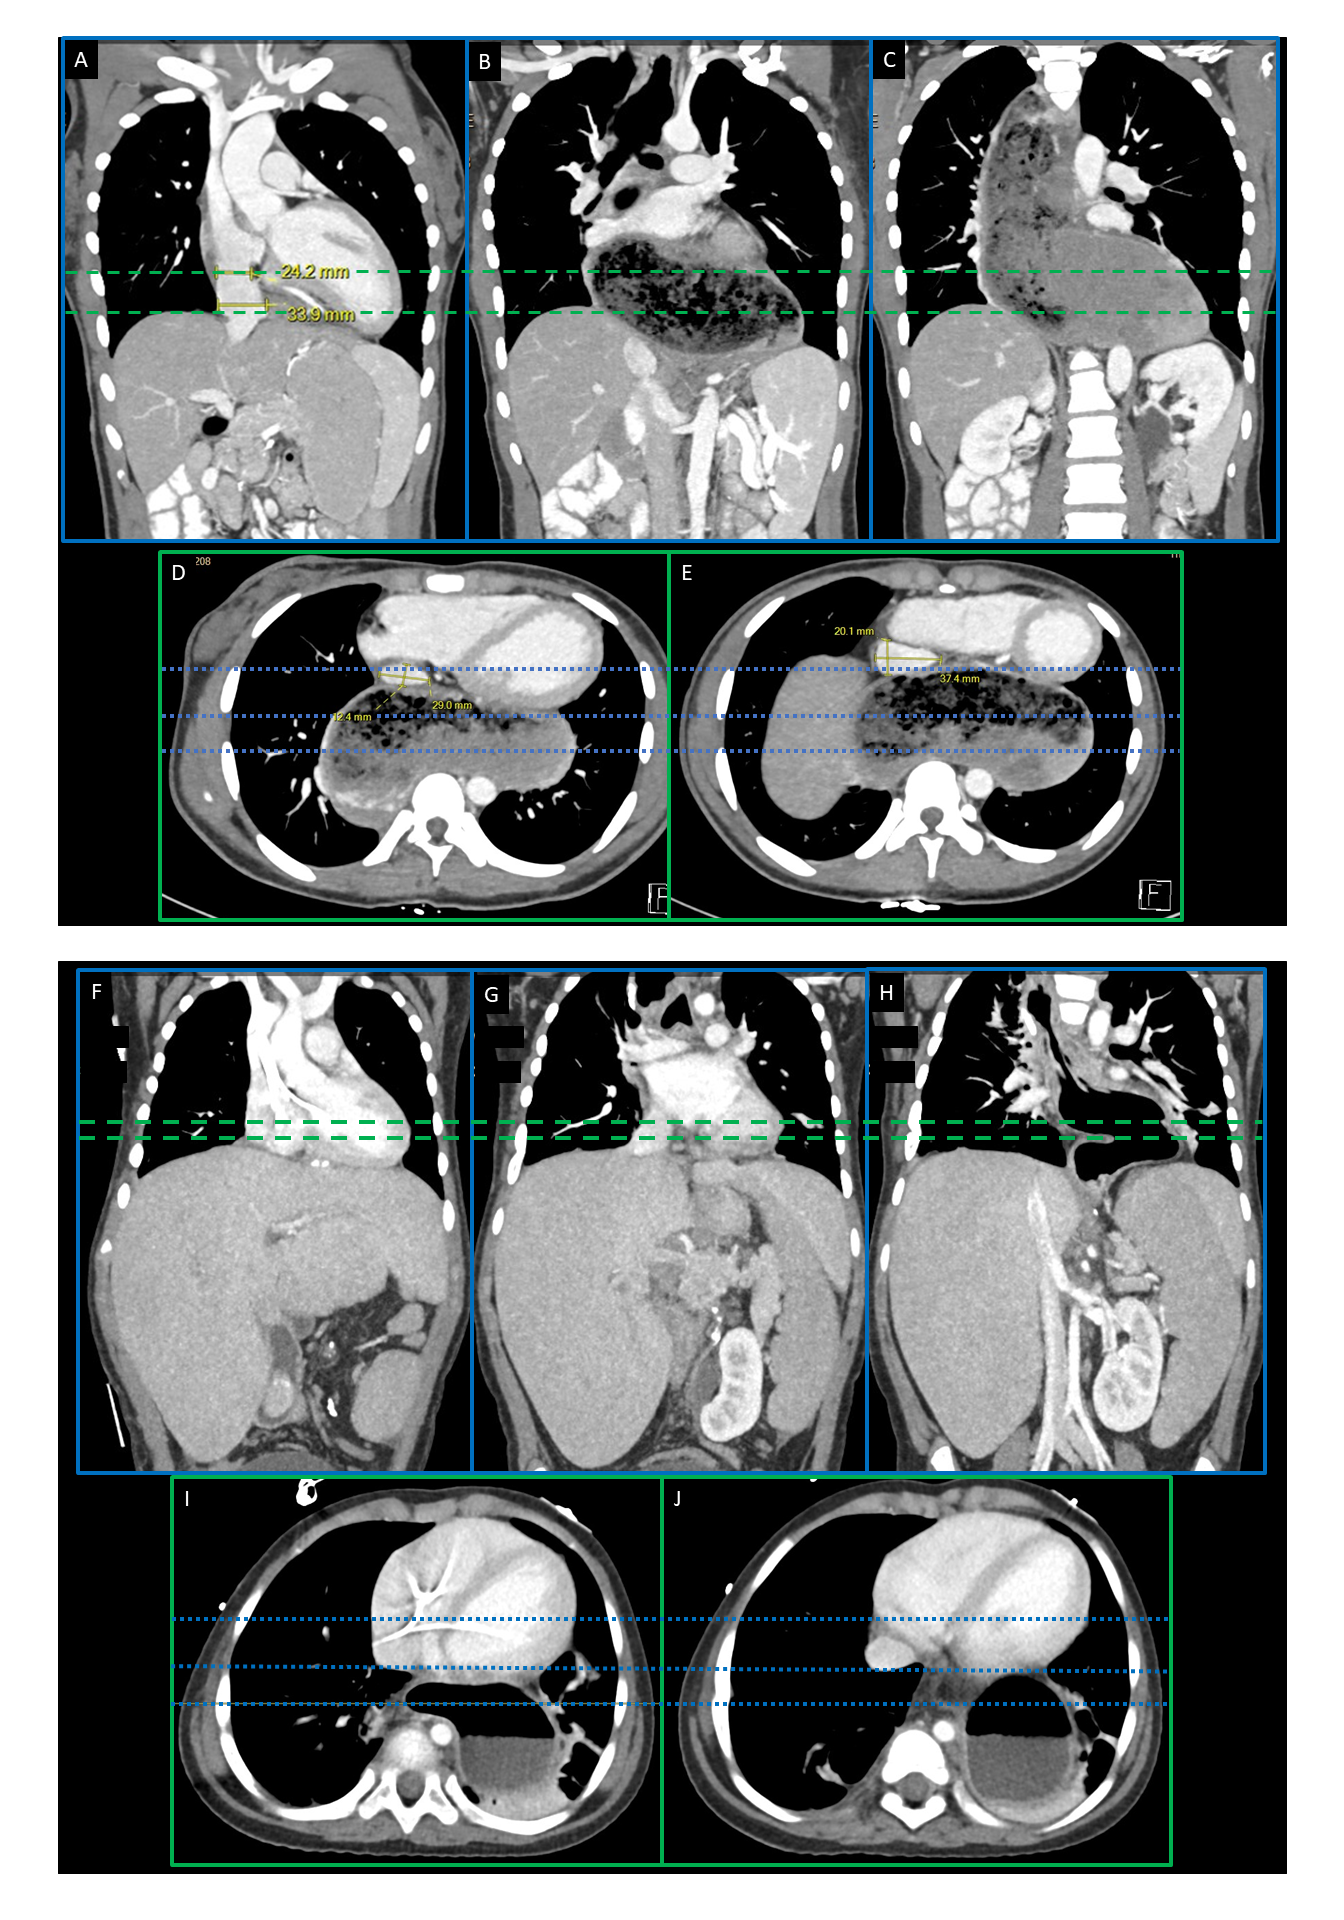

Case 1: A 17-year-old patient with MMIHS, megaesophagus, and liver-small bowel transplant presented with elevated transaminases. Liver biopsy showed congestive hepatopathy without rejection. CT revealed HVOTO due to compression of the thoracic IVC from dilation of the esophagus with retained food. (Figure 1)

Case 2: A 3-year-old with intestinal failure associated liver disease was evaluated for liver-small bowel transplant. She had a history of esophageal atresia status post gastric pull-up and volvulus leading to intestinal failure. Her liver evaluation showed hepatomegaly, early bridging fibrosis, and sinusoidal fibrosis. Imaging revealed no vascular obstructions, but an empty stomach within the thoracic cavity near the posterior heart. The final diagnosis was intermittent extrinsic compression of the thoracic IVC due to dynamic stomach enlargement with food. (Figure 1)